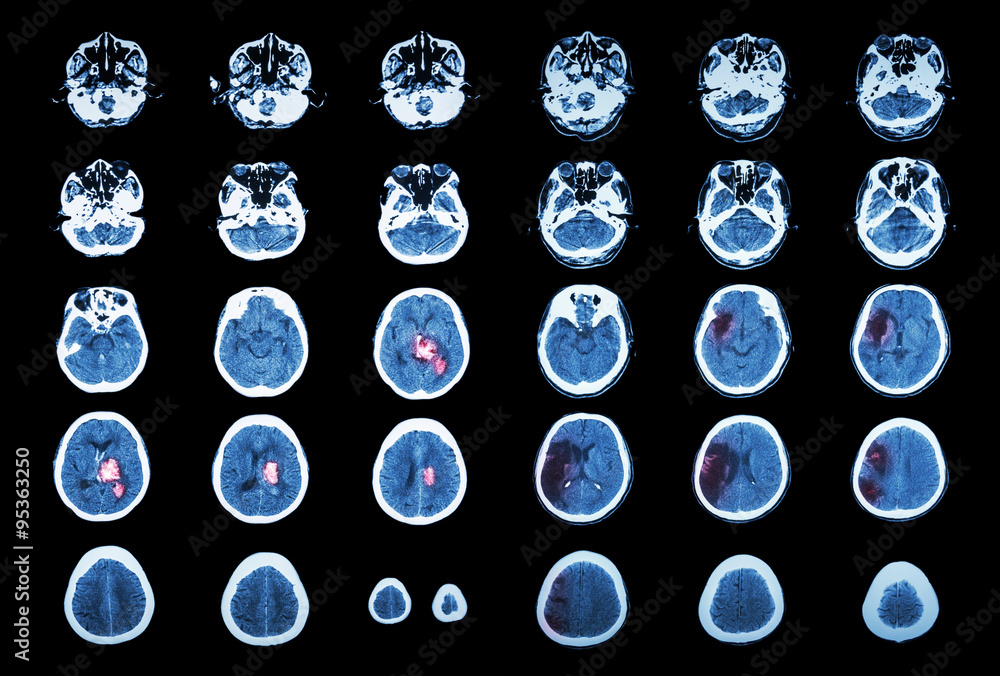

1. 신속한 평가 및 진단: 뇌경색 초기증상과 징후를 신속하게 인식하는 것은 적시에 개입하고 환자 결과를 개선하는 데 필수적입니다. 의료 전문가는 NIHSS(National Institutes of Health Stroke Scale)와 같은 도구를 사용하여 잠재적인 뇌경색 환자를 신속하게 평가하고 컴퓨터 단층 촬영(CT) 스캔 또는 자기 공명 영상(MRI)을 포함한 진단 테스트를 시작하여 진단을 확인하고 유형을 결정해야 합니다.

2. 즉각적인 치료: 뇌경색이 진단되면 뇌 손상을 최소화하기 위해 가능한 한 빨리 치료를 시작해야 합니다. 특정 치료는 뇌출혈 유형에 따라 다릅니다(허혈성 또는 출혈성) 다음과 같이 분류할 수 있습니다.

• 허혈성 뇌졸중(혈전이 뇌로 가는 혈류를 차단하여 발생)의 경우 증상이 시작된 후 처음 4.5시간 이내에 조직 플라스미노겐 활성화제(tPA)와 같은 혈전 용해 약물을 투여하면 결과를 크게 개선할 수 있습니다. 경우에 따라 기계적 혈전 제거술과 같은 혈관 내 절차를 수행하여 혈전을 제거하고 혈류를 회복할 수도 있습니다.

• 출혈성 뇌졸중(뇌 내 출혈로 인해 발생)의 치료는 출혈 조절, 두개골 내 압력 감소, 근본 원인 해결에 중점을 둡니다. 여기에는 혈압을 조절하거나 항응고를 역전시키거나 뇌 부종을 줄이기 위한 약물이 포함될 수 있습니다. 어떤 경우에는 혈액을 제거하거나 손상된 혈관을 복구하기 위해 외과적 개입이 필요할 수 있습니다.